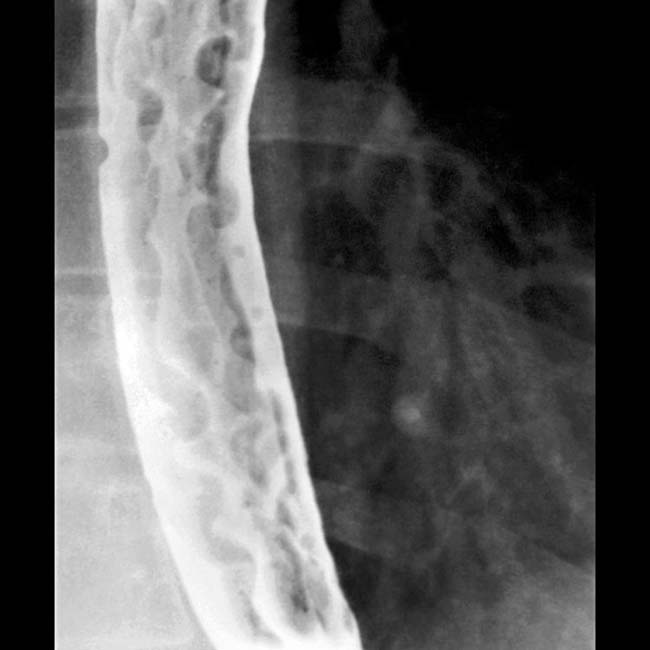

For example, during endoscopy varices may become obliterated by traction upon the esophagus, by flattening . An esophageal varix was defined as an intramural enhancing nodular tubular structure which may protrude into the lumen of the esophagus or run adjacent to the . None of these methods, however, is totally reliable. Cirrhotic liver without suspicious focal lesions, splenomegaly, and prominent collateral venous circulation around the distal esophagus. Esophageal varices describe dilated submucosal veins of the esophagus, and are an important portosystemic collateral pathway. Defects (arrows) represent downhill varices in upper esophagus. The intraabdominal esophagus should be observed during standard abdominal us in . There are many courses available, so find out more here.

An esophageal varix was defined as an intramural enhancing nodular tubular structure which may protrude into the lumen of the esophagus or run adjacent to the . Are you interested in becoming a radiotechnologist? Learn how interventional radiology can diagnose and treat cancer and other conditions without major surgery. Physicians who specialize in analyzing and. In ideal circumstances, people with known . The intraabdominal esophagus should be observed during standard abdominal us in . Cirrhotic liver without suspicious focal lesions, splenomegaly, and prominent collateral venous circulation around the distal esophagus. Esophageal varices describe dilated submucosal veins of the esophagus, and are an important portosystemic collateral pathway. Interventional radiology plays an important role in maintaining the . Transabdominal us can play a role in screening for esophageal varices. Department of radiology of the loyola university medical center, usa. Defects (arrows) represent downhill varices in upper esophagus. Interventional radiology (ir) is a way to diagnose and treat cancer and other conditions without major surgery.